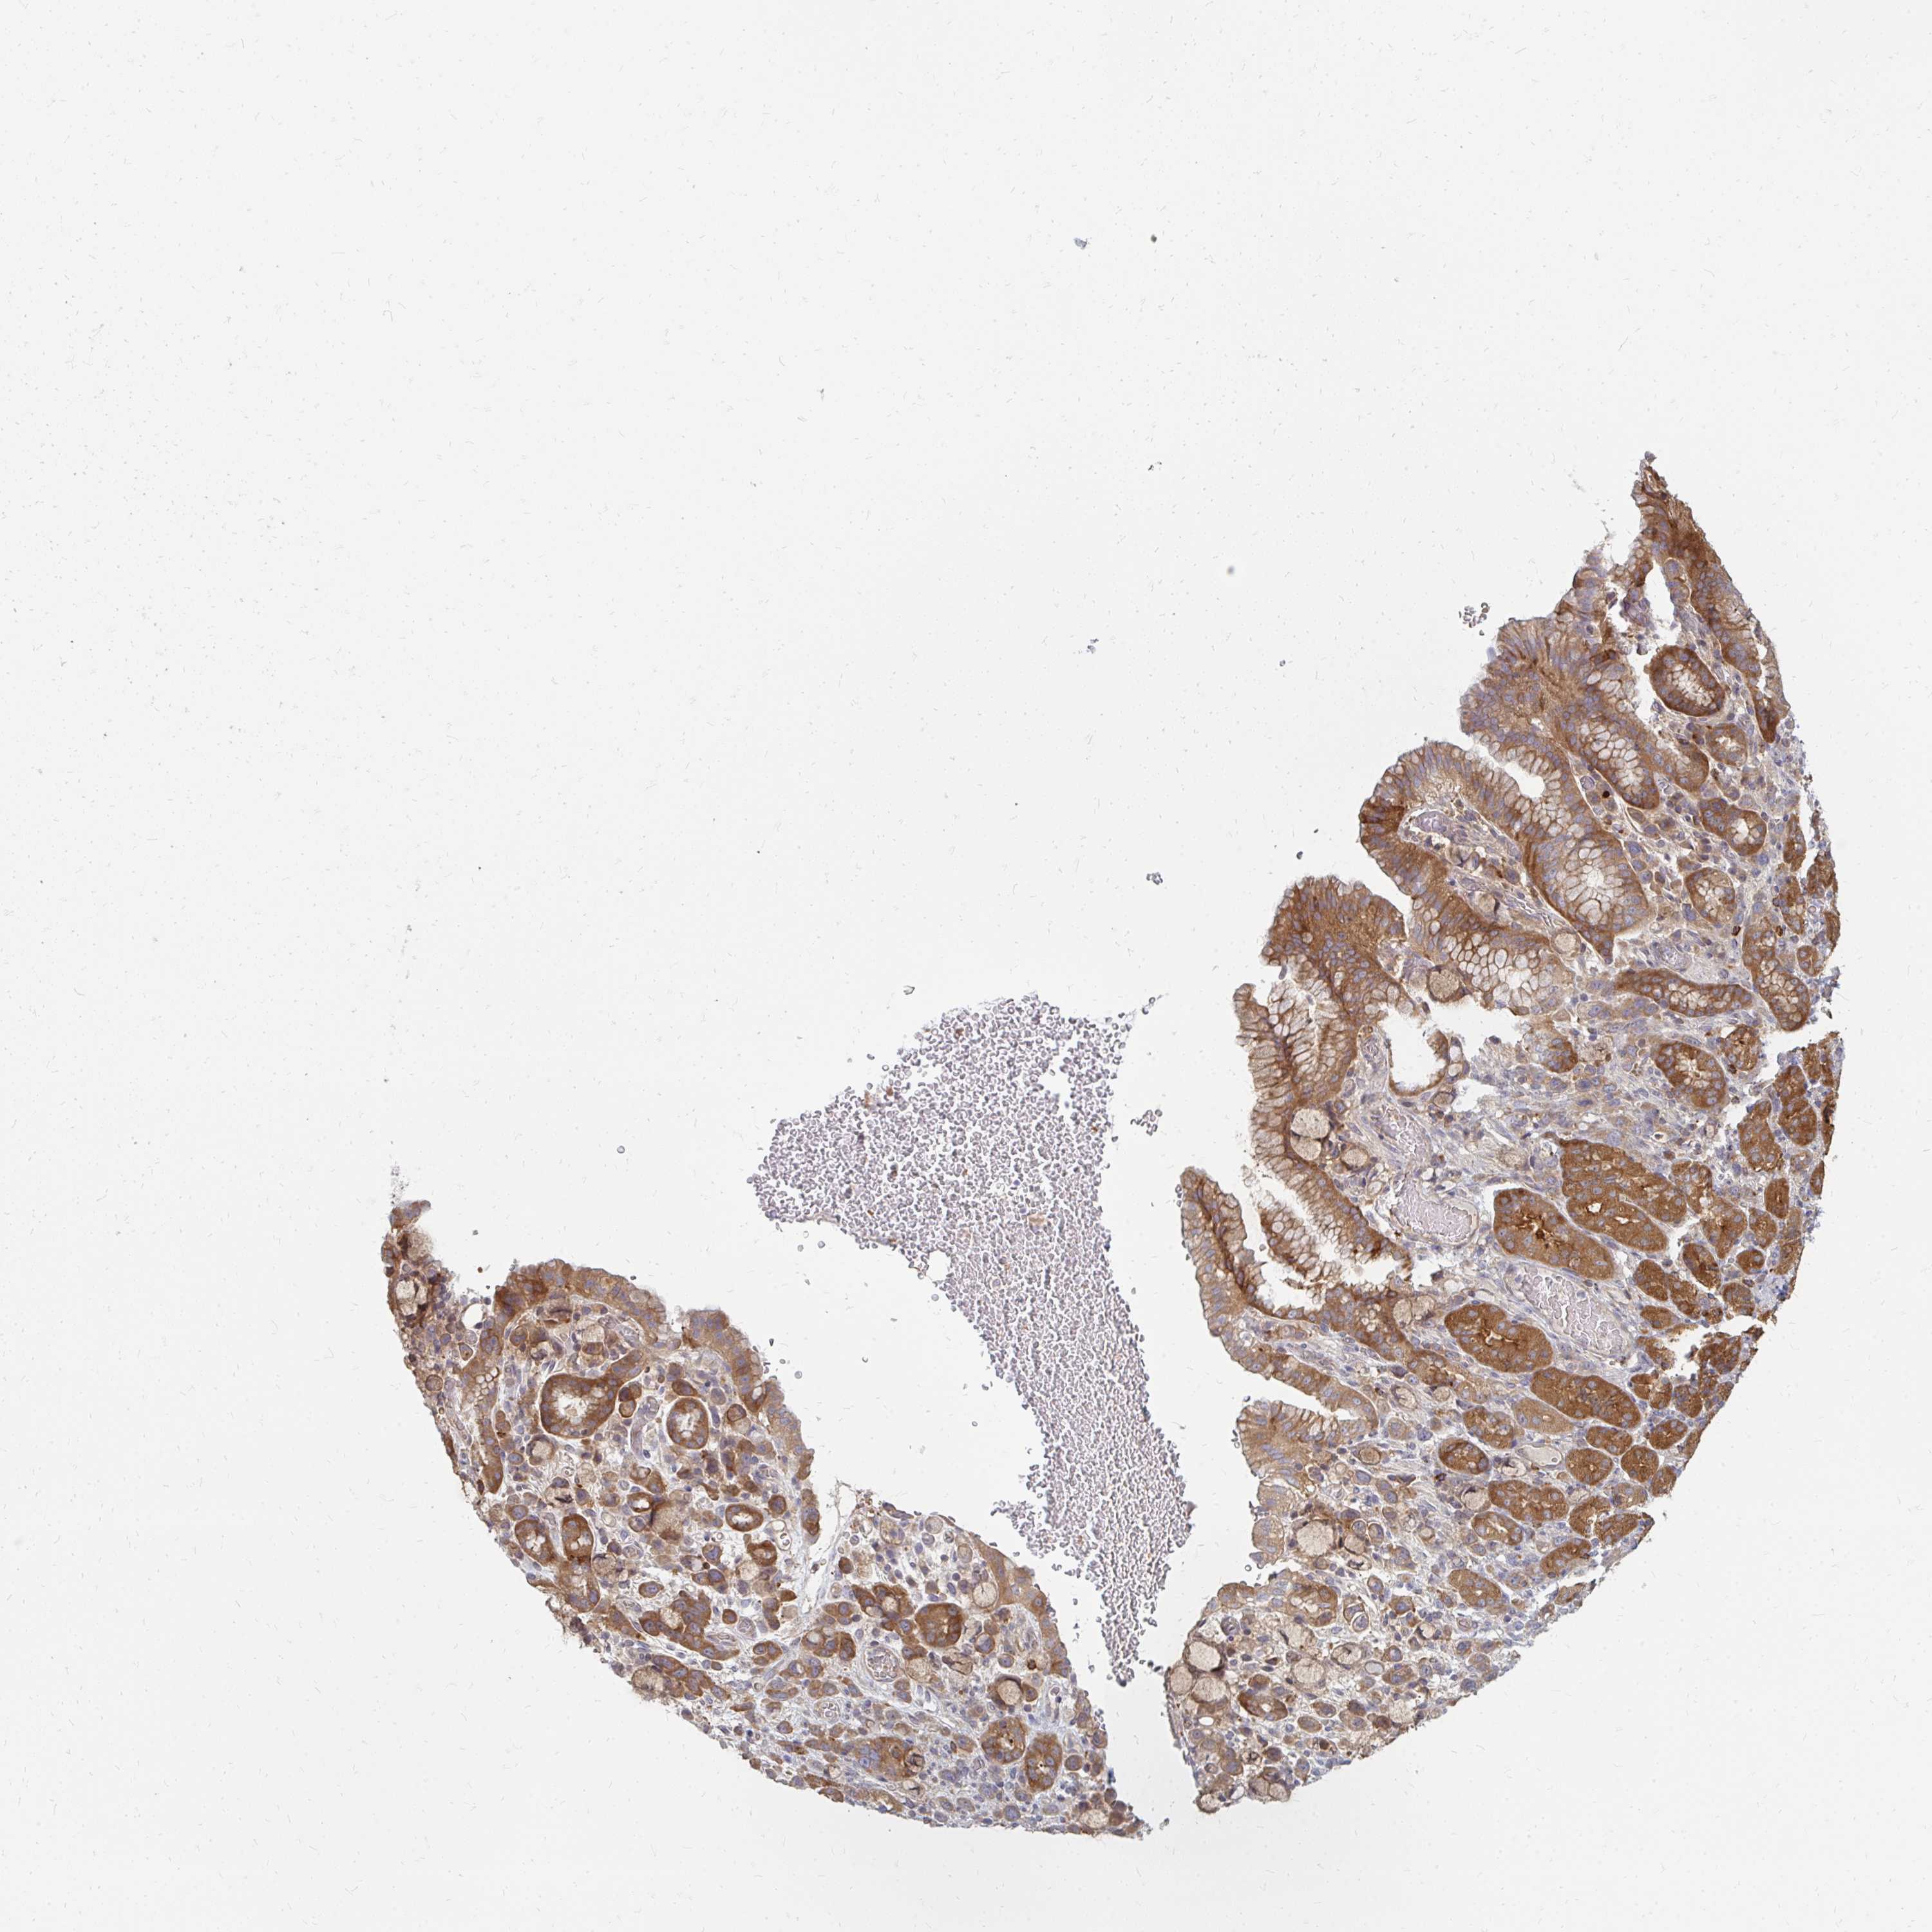

STOMACH CANCER - Protein expressioni

A mouse-over function shows sample information and annotation data. Click on an image to view it in a full screen mode. Samples can be filtered based on level of antibody staining by selecting one or several of the following categories: high, medium, low and not detected. The assay and annotation is described here.

Note that samples used for immunohistochemistry by the Human Protein Atlas do not correspond to samples in the TCGA dataset.

Antibody stainingi

Antibody staining in the annotated cell types in the current human tissue is reported as not detected, low, medium, or high, based on conventional immunohistochemistry profiling in selected tissues. This score is based on the combination of the staining intensity and fraction of stained cells.

Each image is clickable and will lead to virtual microscopy that enables deeper exploration of all samples and also displays staining intensity scores, fraction scores and subcellular localization as well as patient and tissue information for each sample.

Antibody HPA046100

Antibody HPA049212

Staining

High

Medium

Low

Not detected

Intensity

Strong

Moderate

Weak

Negative

Quantity

>75%

75%-25%

<25%

None

Location

Nuclear

Cytoplasmic/membranous

Cytoplasmic/membranous,nuclear

Adenocarcinoma, NOS